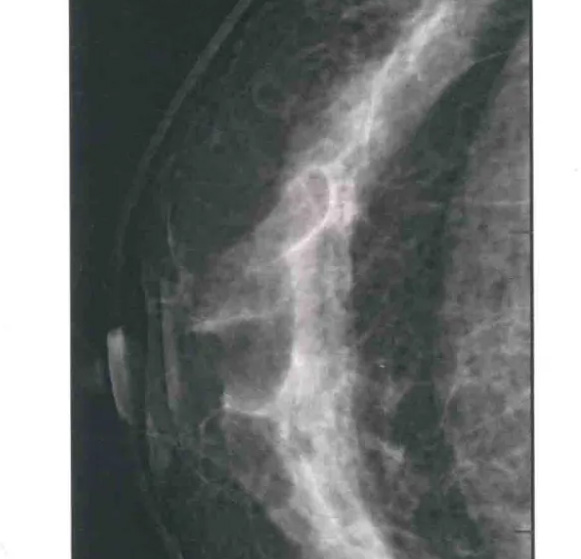

二、圖像顯示要求,含乳腺的基底部及內(nèi)外側(cè)乳腺組織,需要顯示胸肌前緣或胸壁。頭尾位與內(nèi)外斜位乳頭后線長度差≤1厘米;顯示實質(zhì)后的乳腺組織,乳頭位于切線位,乳腺組織重疊;雙側(cè)乳腺頭尾位照片相對放置,則兩側(cè)乳腺呈球形;影像密度和對比度良好,能顯示0.1毫米細(xì)小鈣化,清晰沒有偽影異物、運動偽影和切割偽影等。